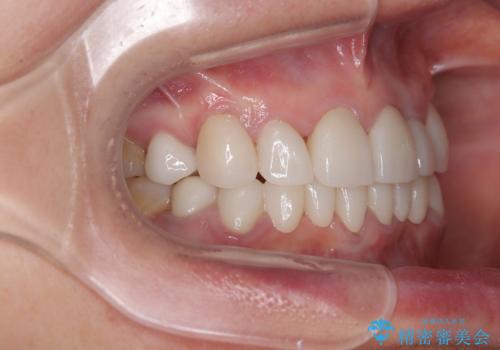

色や歯列が整ったことはもちろん満足いただけましたが、上顎の舌側転位していた前歯が綺麗に整ったことで違和感が減ったことを非常に喜んでいらっしゃいました。